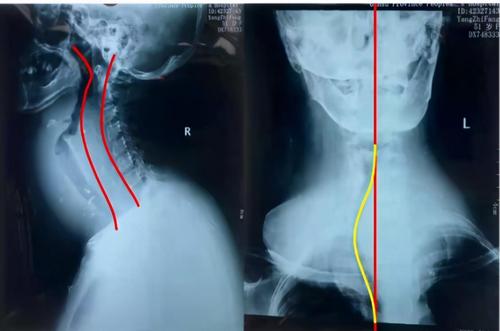

颈椎解剖结构图解